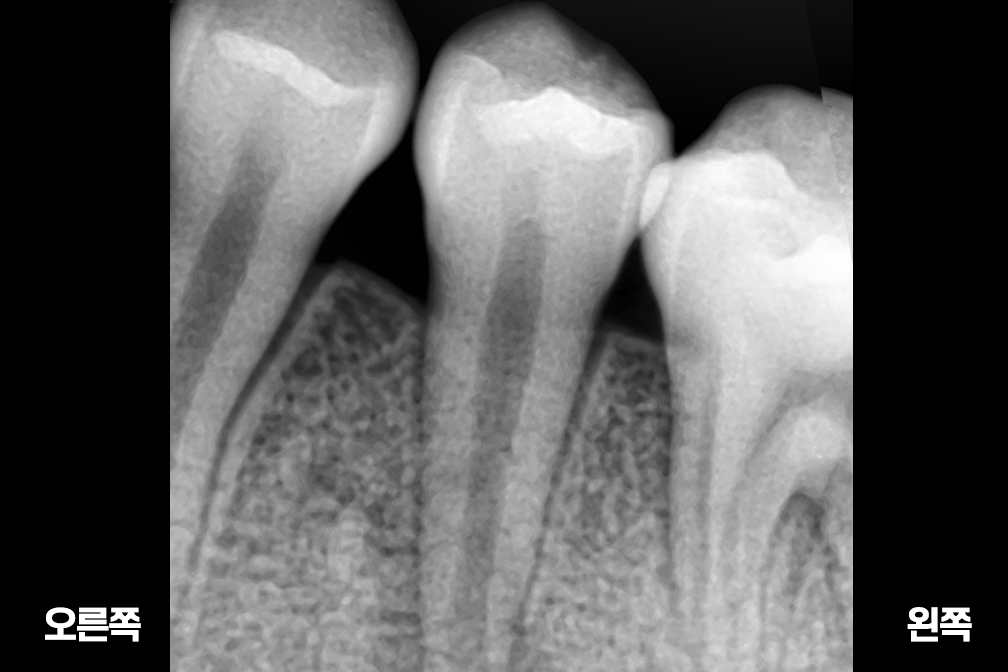

After 2025년 6월 25일